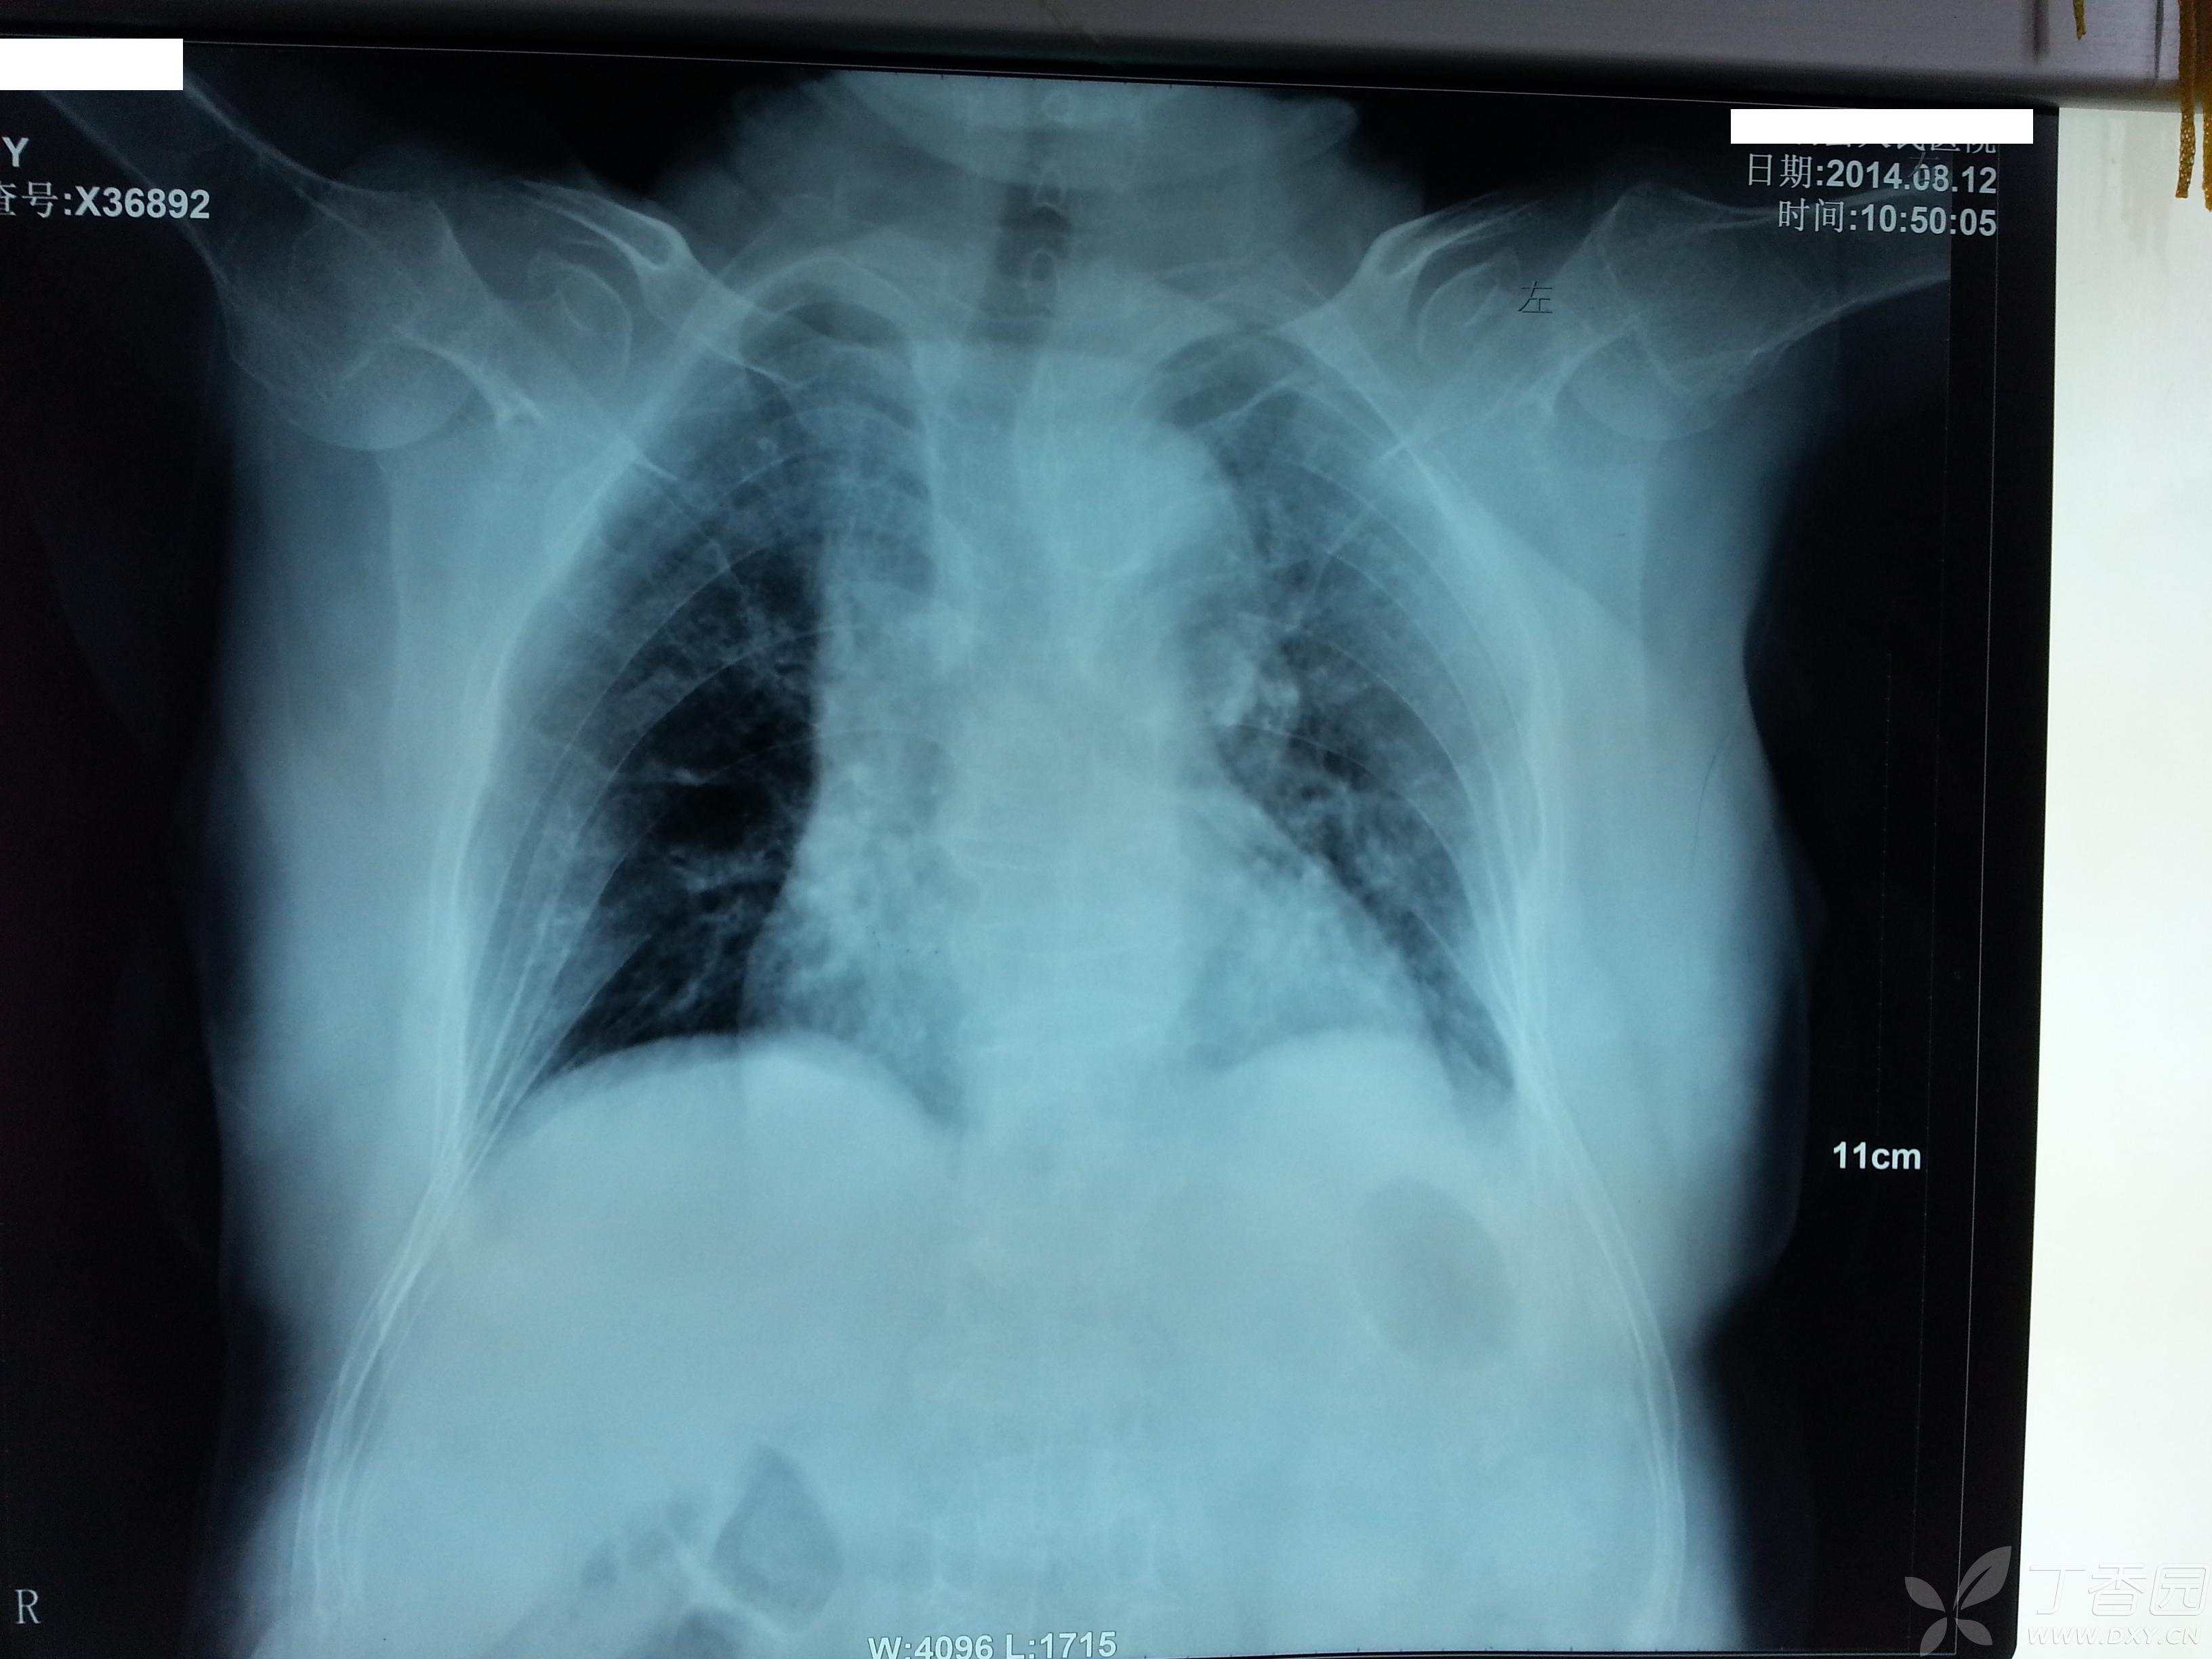

患者62岁女性,无明显外伤史,右髋关节疼痛活动受限1年,加重半年入院,患者一年前无明显诱因出现右髋关节疼痛,活动受限,未到医院诊治,自行以腰椎间盘突出症在家治疗,休息,口服药物治疗,无效,但可以扶拐行走。

查体:心肺腹未见明显异常,右下肢短缩3厘米,右髋关节活动受限,右下肢无明显水肿,无明显感觉异常,膝上10厘米右侧大腿周径较左侧减少约2厘米,右小腿周径较左侧减少约1厘米,末梢血运好好。X片如下,右股骨颈陈旧性骨质,髋臼侧及股骨侧继发骨质疏松。CT检查显示右股骨颈骨质,股骨近端骨质未见明显破坏。